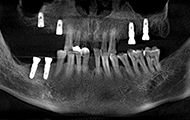

缺了8颗牙,名副其实的“缺牙一颗带坏全口”,在检查后,我右边的第一缺牙已经有严重的骨萎缩了,是“纸片骨”,种牙难度很大,我从湖南跑到深圳,可以说一路都在对比医院和方案。

我听过的拒诊理由很多,有“年纪太大了,怕风险高”,“你这骨量不好,种牙难度太大了”,“缺牙数太多,难度也大,可以做但是很贵,你还是换其他方法吧”,在这里我看到了希望…医生技术好,还会为我省钱,给过做种植体+冠桥,缺了8颗大牙,种6颗种植体就够了。

面对我参差不齐的骨量,整个团队都围绕着我想方案,最终确定了给我骨粉骨膜搭配植骨的方式重新夯实我的骨量,老爷子我很感恩。

过去十天了,今天去拆线,然后歇上一段时间,我的手术创口比较多,难免要缝合。种植体重新拍摄了CT,植入良好,医生今天给我检查,种植牙术后并没有肿胀,恢复的还算不错,看来我老骥伏枥,体质还不错,也感谢医生种牙技术的高超,种植体都是微创的手术,种植牙的创口减小了,种植牙术后就更容易恢复了。